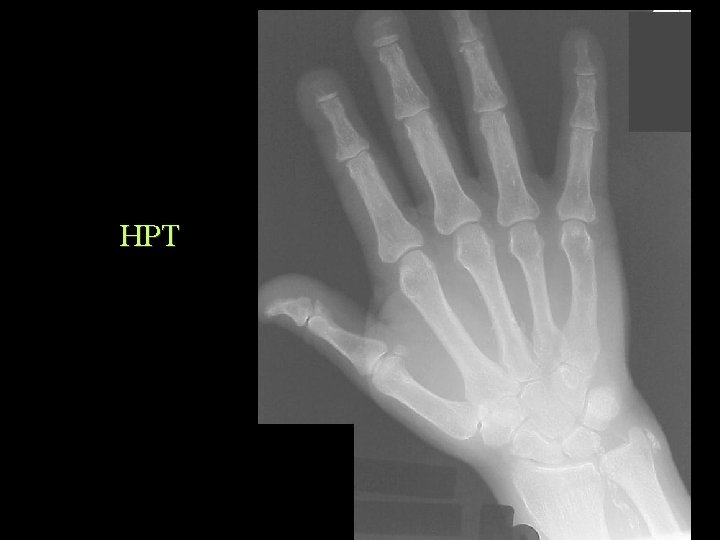

Soft Tissue Calcification By Cause Metastatic Calcification • Hyperparathyroidism • • • Hypoparathyroidism Renal Osteodystrophy Hypervitaminosis D Milk Alkali Sarcoidosis Massive bone destruction – Mets. , Myeloma, Leukaemia

HPT